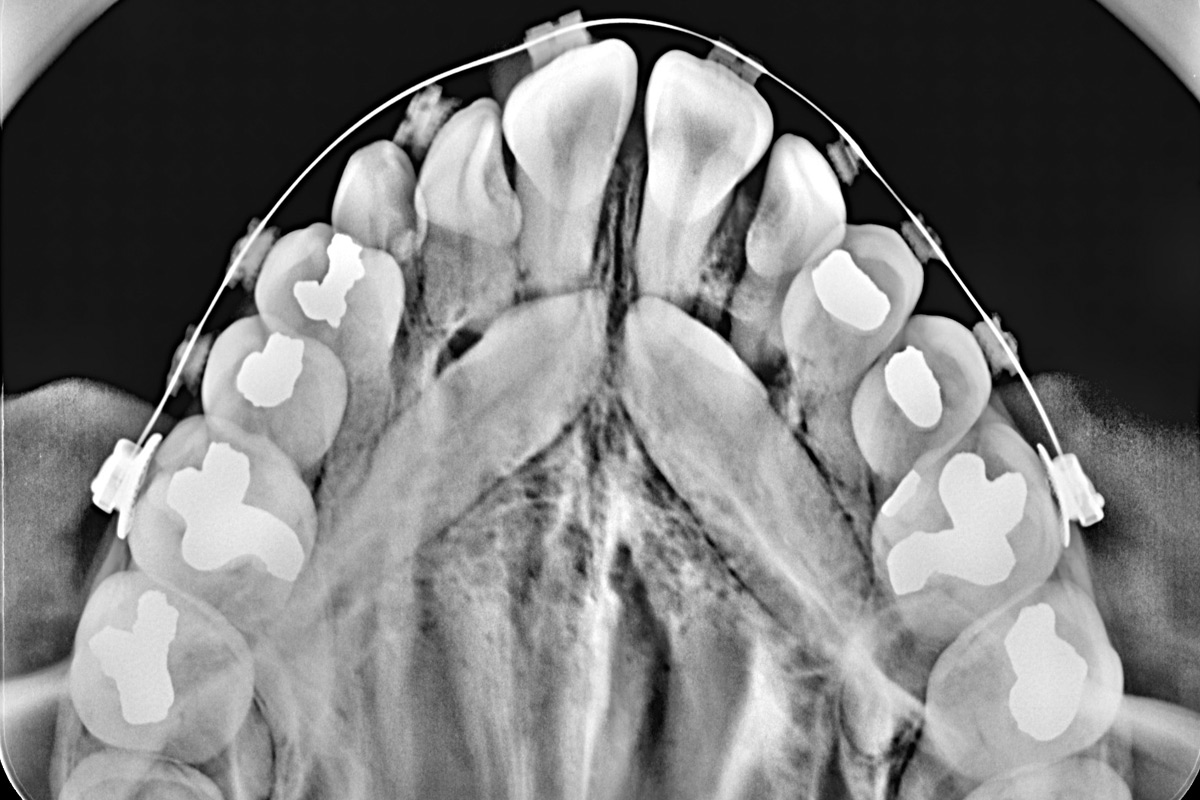

La Radiografía Intraoral Digital es una técnica de imagenología dental que permite obtener imágenes detalladas del interior de la boca, centrándose en dientes específicos, raíces y estructuras óseas cercanas. Esta tecnología es esencial en el diagnóstico y tratamiento de diversas condiciones dentales, ya que proporciona una visión clara y precisa de las áreas más pequeñas y difíciles de observar con métodos convencionales.

Este tipo de radiografía es fundamental en una amplia gama de procedimientos odontológicos. Es ideal para detectar caries, incluso en sus etapas más tempranas, así como para evaluar la salud de las raíces dentales y el hueso que sostiene los dientes. También se utiliza para monitorear el desarrollo de dientes en niños, examinar áreas problemáticas en tratamientos de conductos, y planificar procedimientos de restauración dental, como coronas, puentes o empastes. La precisión de la radiografía intraoral digital permite un diagnóstico más temprano y un tratamiento más efectivo.

- Oclusal